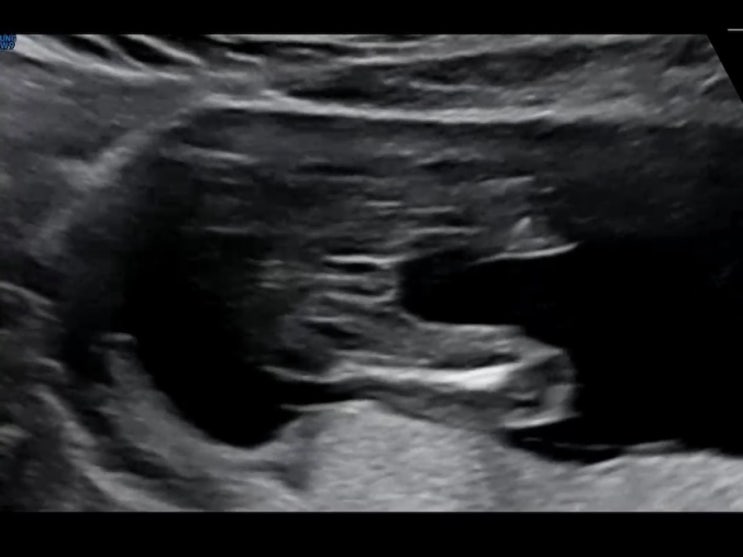

둘째 임신 17주 성별 확정 장꾸맘 성별 반전은? 경산모 태동 느끼다

둘째 임신 12주~16주 1차 기형아검사 옹글이 성별 초음파

옹 하 ? 벌써 17주를 앞두고 있는 둘째 옹글이 첫째를 키우다보니 둘째는 진짜 순식간이네요... 11주부...